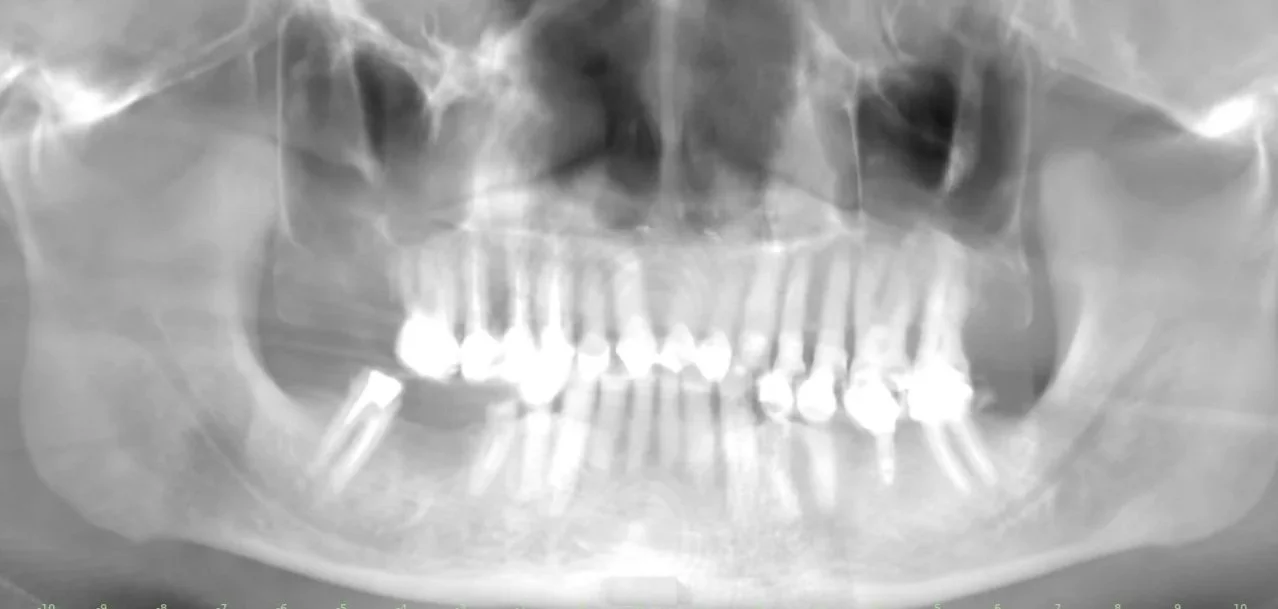

Fotografías iniciales

Estudios previos